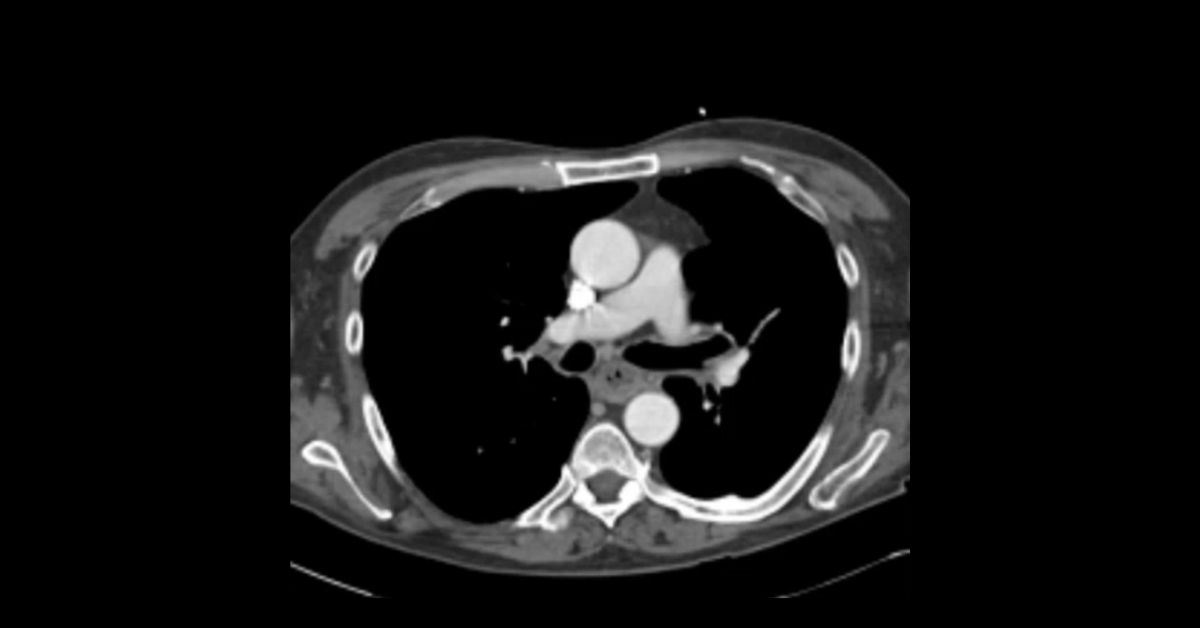

Pulmonary Granulomatous & Cavitary Lesions

Cases of pulmonary neoplasm, biopsy complications, and esophageal pathologies with discussions of their imaging diagnosis and physiologic complexities.

1. Learn the imaging appearance of numerous esophageal pathologies.

2. Understand the potential complications of pulmonary biopsy procedures.

3. Appreciate the many locations and imaging appearances of varices.